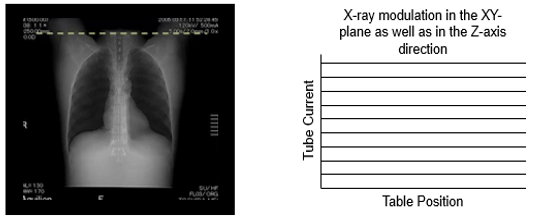

mA Modulation

Automatic correction adjusts dose as a function of patient size and the anterior-posterior and lateral directions. The lateral projection generally encounters more tissue thickness than a PA view. This is known as mA modulation and the mA is increased and decreased as the patient is scanned. Most systems use an average mA to calculate the CTDIvol.

This is an automatic dose-response based on patient anatomy (scout view). Since the human body is not cylindrical, its contours and tissue densities must be taken into account.

Automatic correction adjusts dose as a function of patient size and the anterior-posterior and lateral directions.